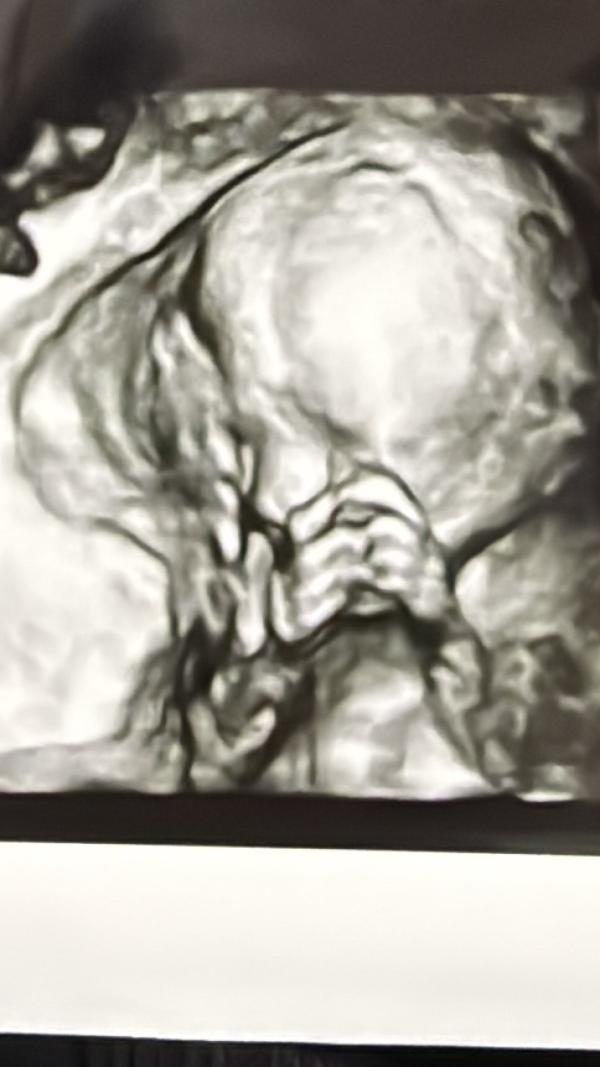

Всем 🫶🏼 от маленького человечика❤️ Поведение как у девочки, все время лицо прятала и еще и спала вообще к диир турбатаха 😂сходила на 2 скрининг в центромед и Томская такую фотографию подарила хотя у меня было 2Д🥰 С малышкой все хорошо вес 290гр. До сих пор не верю что у меня растет целая жизнь если бы не постоянная сонливость и лень то беременный да курдук сананыам суоха этэ😂